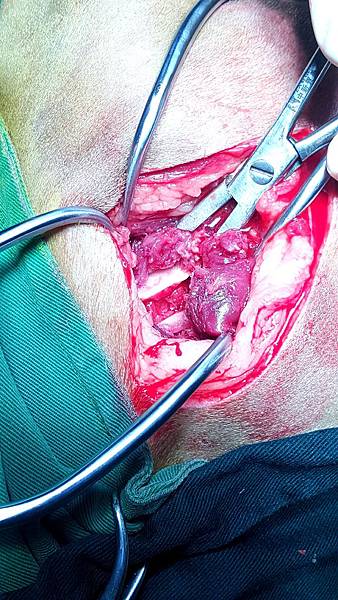

經由手術後治療

恢復得很棒

手術後一個月